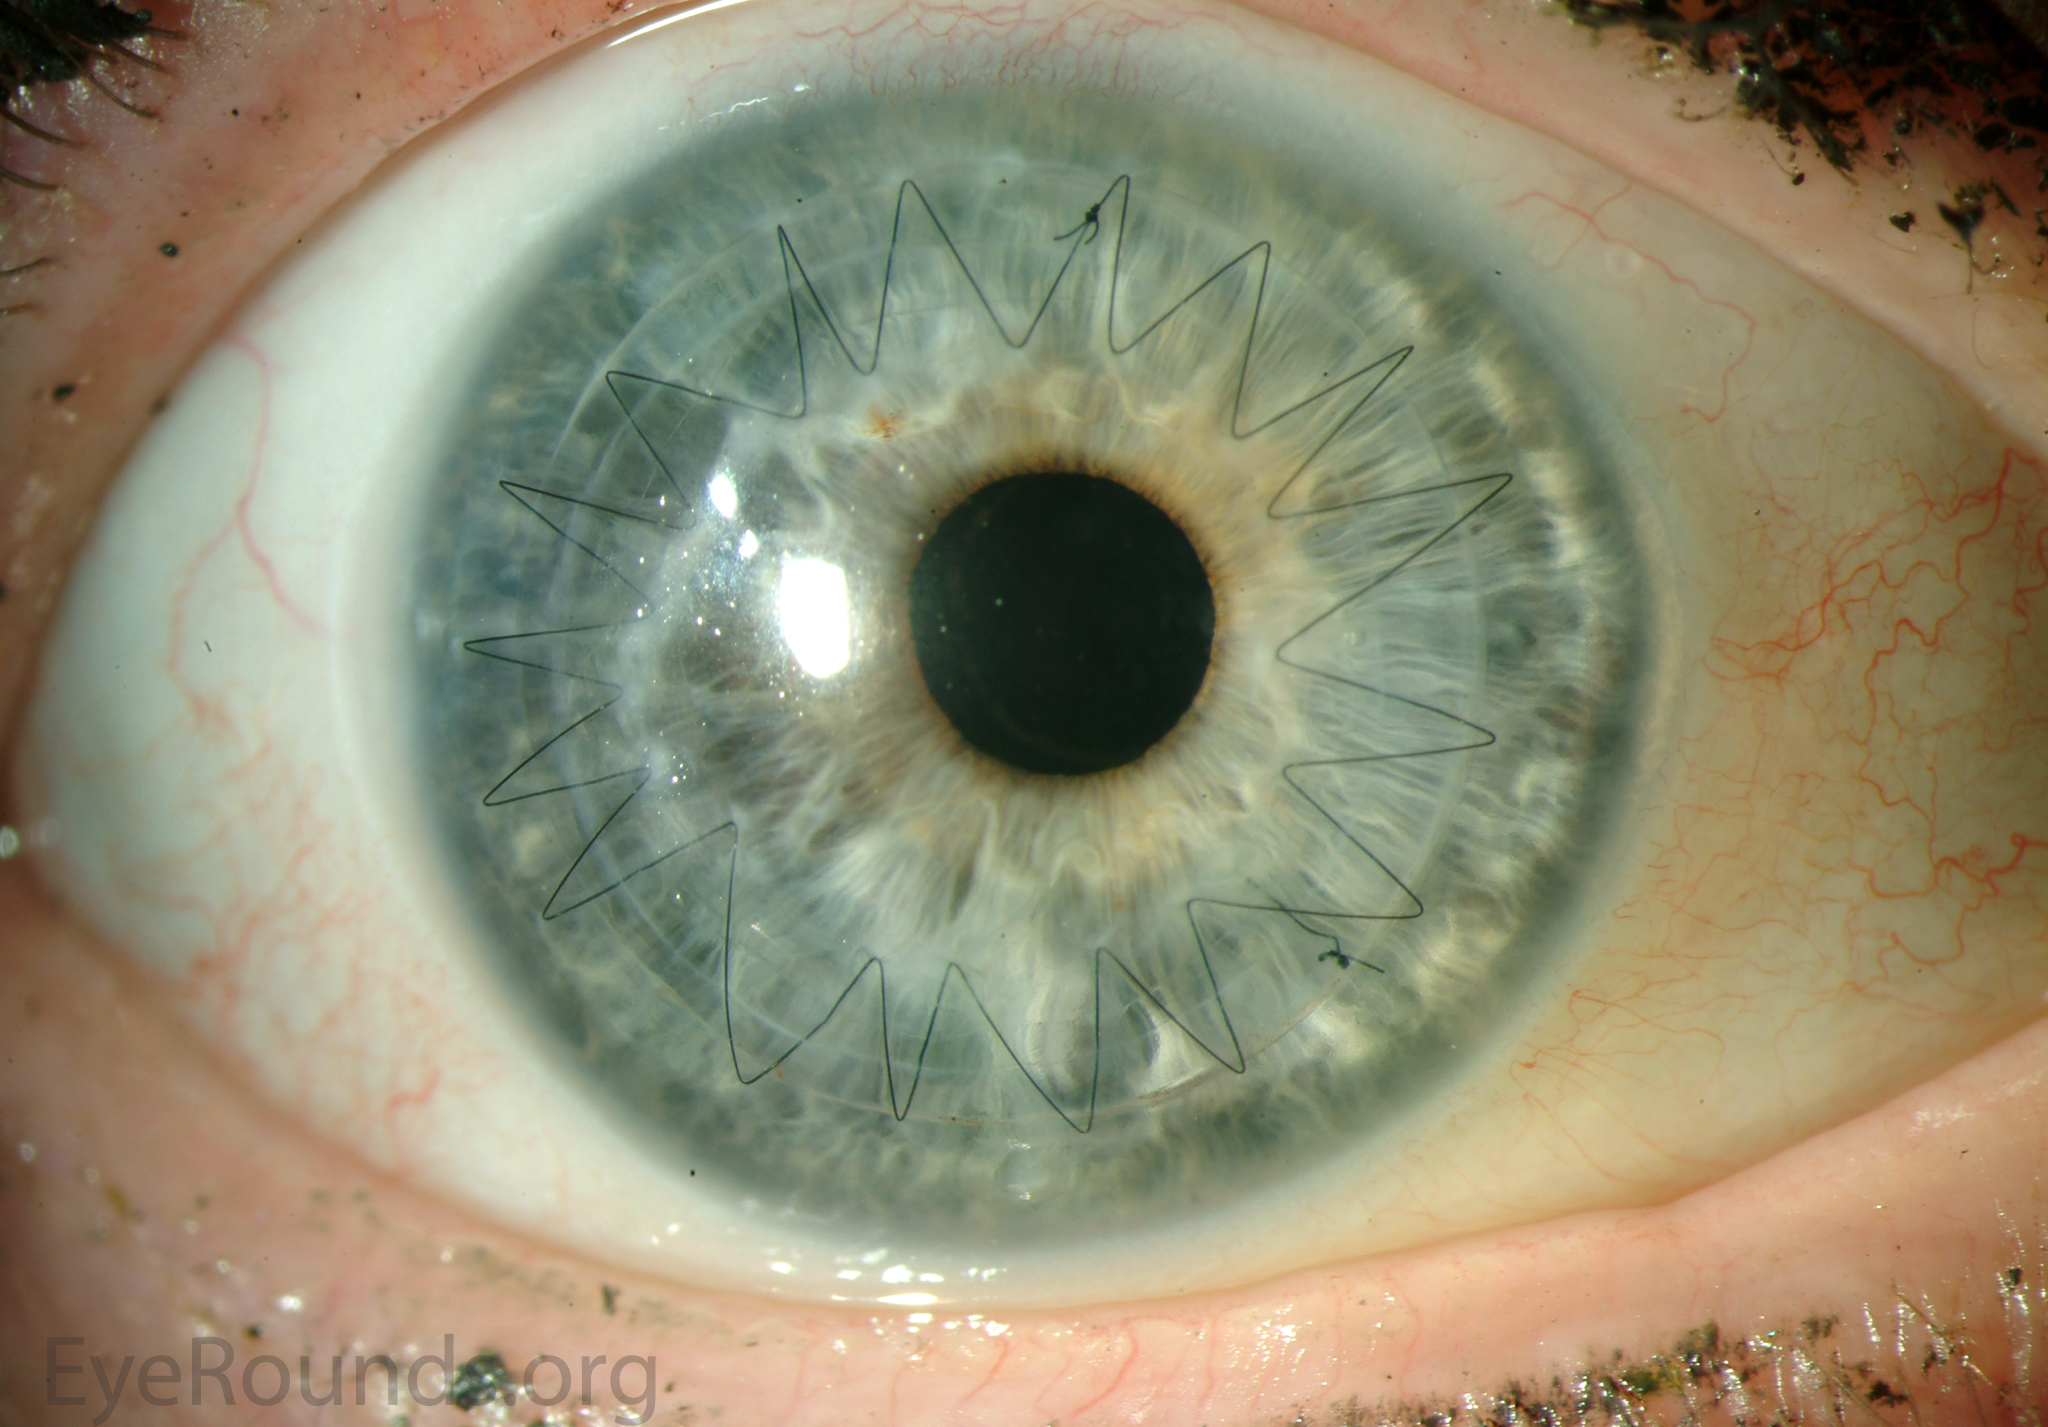

DALK is a partial-thickness cornea transplant procedure that involves selective transplantation of the corneal stroma, leaving the native Descemet membrane and endothelium in place. A trephine of an appropriate diameter is used to make a partial-thickness incision into the patient's cornea, followed by pneumodissection or manual dissection of the anterior stroma. This is followed by placement of a graft prepared from a full-thickness punch in which the donor endothelium-Descemet membrane complex has been removed. The intention is to preserve the patient's Descemet membrane and endothelium. Similar to PK, the graft is secured with interrupted and/or running sutures (Figure 5) and these are then selectively removed post-operatively (Figure 6).